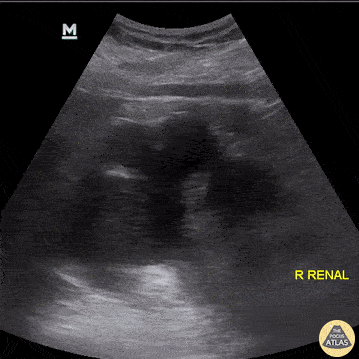

THE VIEWS: RIGHT KIDNEY

Longitudinal Axis

Point the probe indicator towards the patient’s head.

Place your probe at the Right Mid-axillary Line around the 10th to 11th intercostal space.

Center the kidney on the ultrasound screen.

Slowly tilt/fan the probe anteriorly and posteriorly to assess the entire kidney.

The normal size of an adult kidney is around 10-11cm in the longitudinal view.